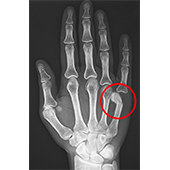

Boxer’s Fracture

A boxer’s fracture is a break in the neck of the fifth metacarpal bone of the hand (below the pinky finger) close to the knuckle. The hand is composed of 3 types of bones: carpal or wrist bones, metacarpals or long hand bones, and phalanges or finger bones. Metacarpals consist of five long bones that connect the carpal with the phalanges. Structurally, metacarpal bones can be divided into four parts: base, shaft, neck, and head. In some cases, the broken bone can protrude through the skin and is called an open fracture.